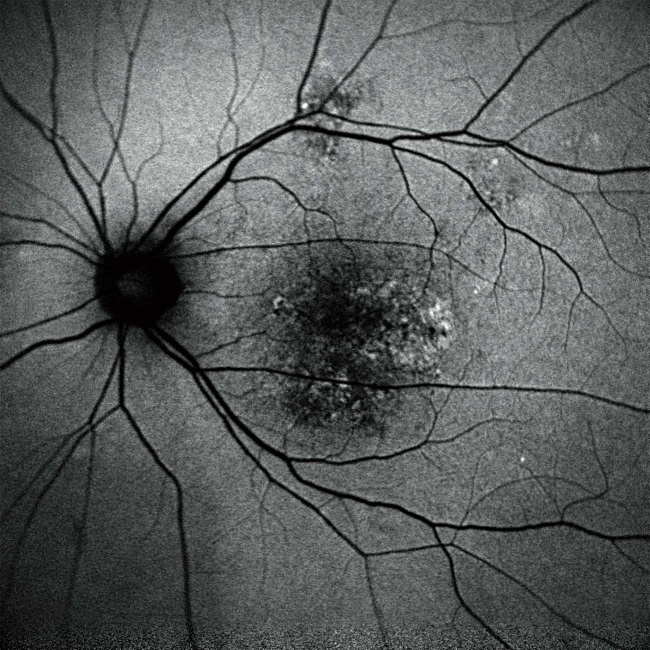

・蛍光眼底造影検査(FA/IA)

フルオレセインやインドシアニングリーンという造影剤を使って眼底の網膜血管や脈絡膜血管を撮影する検査です。OCTAではとらえられない微細な病変や血管炎や蛍光漏出点を描出できます。広角での検査が可能ですので網膜周辺部の病変まで捉えることができます。このミランテは2つの造影剤を使って2種類の造影検査を同時に行うことができます。主な対象疾患は、加齢黄斑変性、網膜静脈閉塞症、糖尿病網膜症などです。

・眼底自発蛍光

2つの波長で網膜色素上皮における自発蛍光(造影剤を使わない)を発するリポフスチン(老廃物)を観察し網膜色素上皮の非侵襲で検査できます。主な対象疾患は、加齢黄斑変性、網膜色素変性症などです。